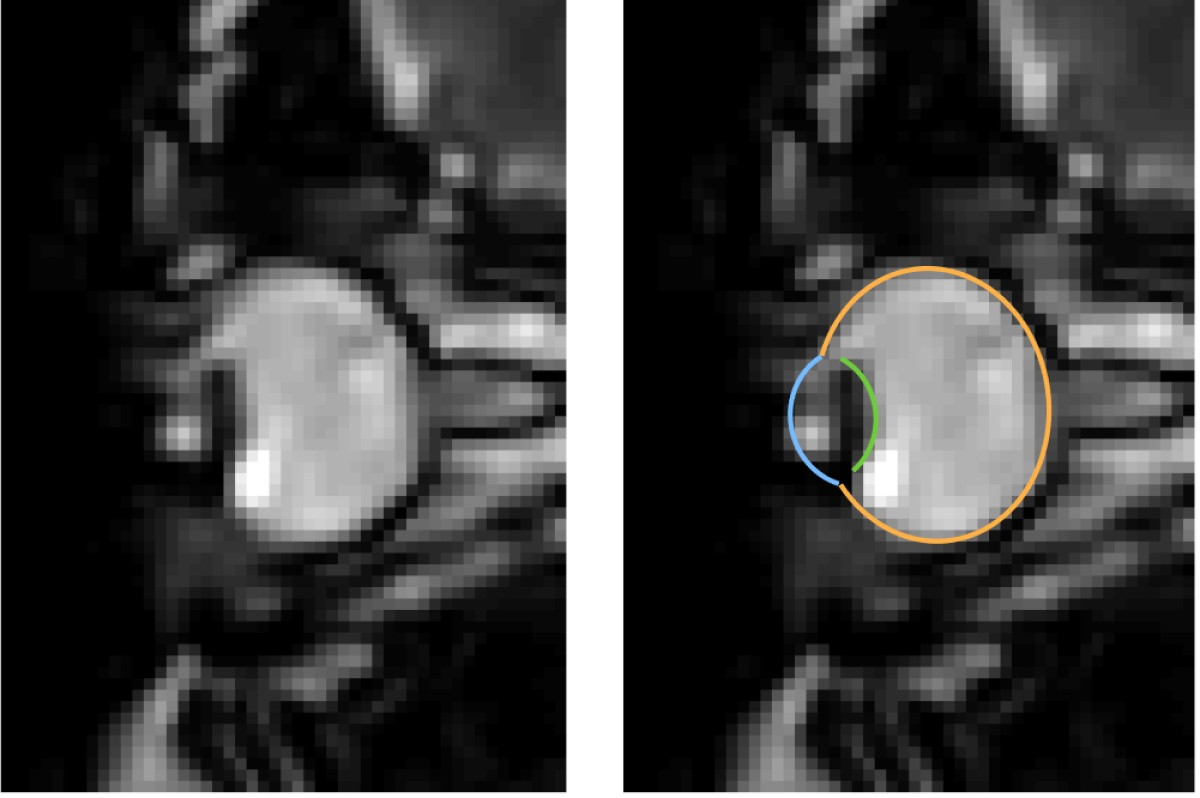

MRT-Aufnahmen von Augenbewegungen beim Blinzeln: Das Auge wird in die Augenhöhle zurückgezogen. Das linke Bild zeigt jeweils nur die dynamischen MRT-Daten, das rechte zusätzlich dazu die Segmentierung des Auges durch den MREyeTrack. Die Fotostecke bestehend aus sechs Bildern stellt die Augenbewegung dar.© WWU - Johannes Kirchner

Augenbewegungen werden typischerweise mit sogenannten Eyetrackern gemessen, also Hochgeschwindigkeitskameras, die die Position der Pupille filmen. Einige Aspekte von Augenbewegungen lassen sich damit jedoch nicht messen. „Es ist uns gelungen, ein Verfahren zu entwickeln, das Augenbewegungen in bisher unerreichter zeitlicher Auflösung mit Echtzeit-MRT-Sequenzen misst. So konnten wir mit unserer Methode zum Beispiel zeigen, dass der komplette Augapfel beim Blinzeln in die Augenhöhle zurückgezogen wird“, erläutert Autor Johannes Kirchner, wissenschaftlicher Mitarbeiter am Institut für Psychologie der WWU. Die Methode haben die WWU-Wissenschaftler mit der Co-Autorin Prof. Dr. Tamara Watson von der Western Sydney University entwickelt.

MRT ist ein relativ langsames Verfahren, die zeitliche Auflösung bewegt sich normalerweise im Bereich von Sekunden oder Minuten. Augenbewegung hingegen sind schnell und dauern typischerweise nur ein paar Dutzend Millisekunden an. Entwicklungen in den vergangenen zehn Jahren haben es jedoch ermöglicht, 2-D-MRT-Aufnahmen mit bis zu 20 Millisekunden zeitlicher Auflösung zu produzieren. Diese ultraschnellen Verfahren kommen vor allem bei der Herzbildgebung zum Einsatz und werden bislang nicht auf die Messung von Augenbewegungen angewandt. „In unseren Aufnahmen haben wir eine zeitliche Auflösung von etwa 35 Millisekunden erzielt. Da bei einer gesamten Messzeit von ein paar Minuten mehr als 10.000 Bilder entstehen, braucht man, um tatsächliches Eyetracking zu betreiben, einen vollautomatischen Algorithmus, um diese Daten auszuwerten“, schildert Mitautor Prof. Dr. Markus Lappe, Leiter des Lehrstuhls für Allgemeine Psychologie und kognitive Neurowissenschaften am Institut für Psychologie der WWU. „Mit ‚MREyeTrack’ haben wir einen solchen sogenannten Segmentierungsalgorithmus entwickelt, der es erstmals ermöglicht, vollautomatisch Position und Orientierung des Auges in jedem einzelnen Bild zu analysieren.“